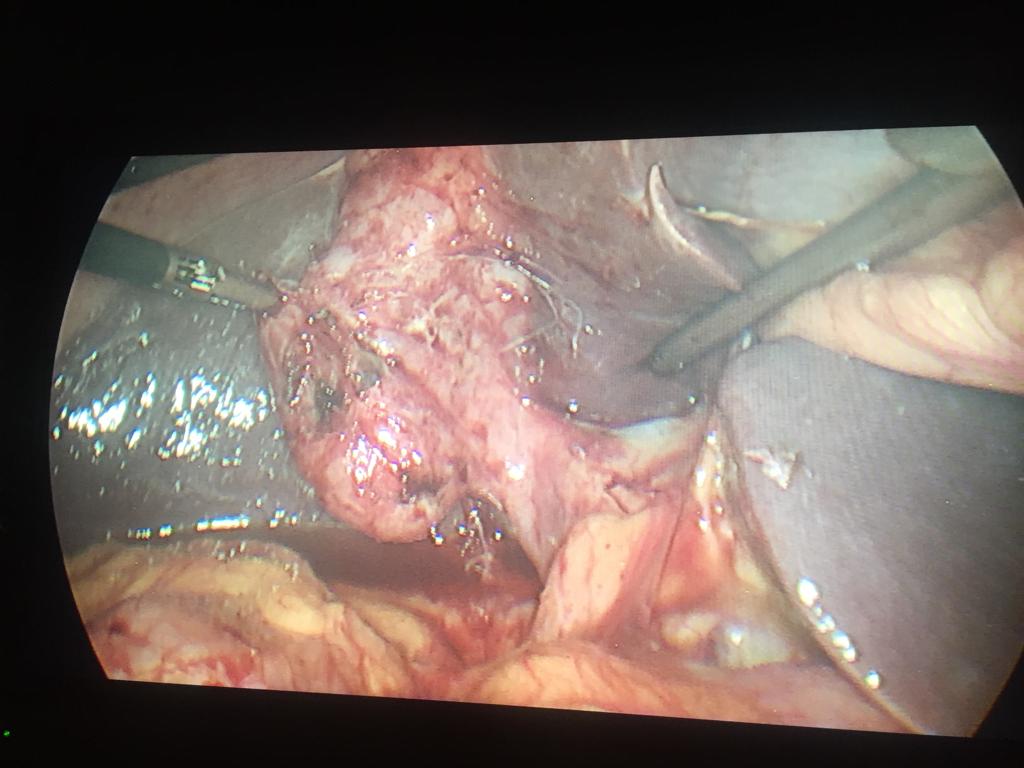

Acute Cholecystis, Mucocele Gallbladder with big stone at the neck. Completely done Laparoscopically